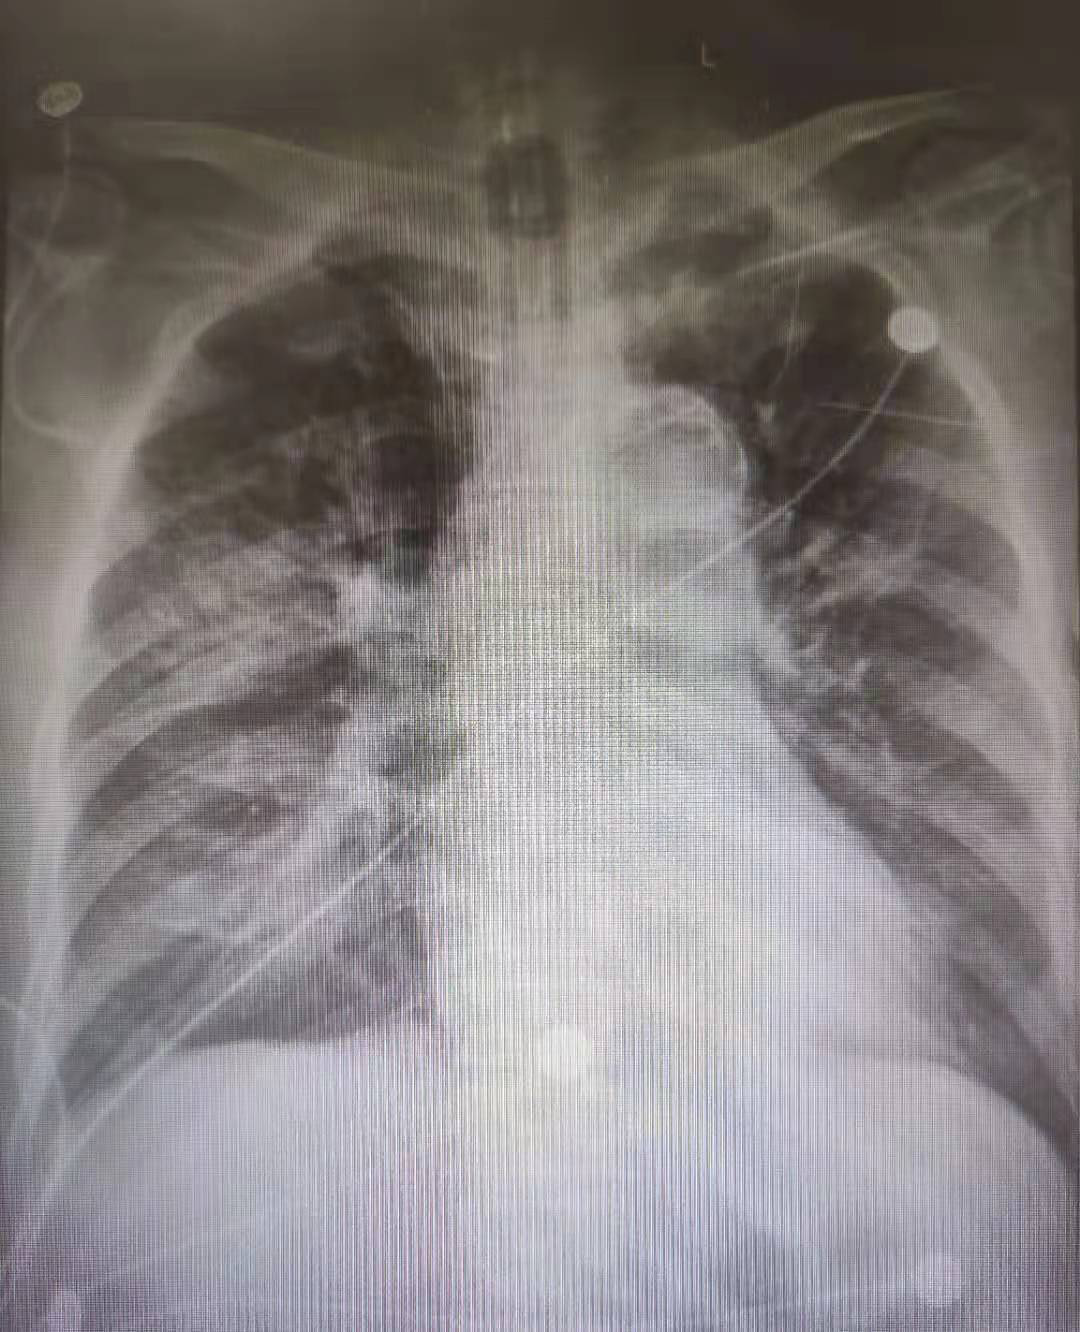

患者李大爺,因重癥肺炎、呼吸衰竭入院接受治療。為確保老人得到及時醫(yī)治,科室專家對李大爺進(jìn)行了全面的檢查。通過檢查,醫(yī)生發(fā)現(xiàn)李大爺張口度只有1.5橫指、舌體肥大、頸部強(qiáng)直、不能充分后仰,屬于典型的困難氣道;同時,血?dú)夥治鎏崾净颊邍?yán)重缺氧及二氧化碳潴留。這些因素導(dǎo)致手術(shù)耐受性差、風(fēng)險大。

針對李大爺病情的特殊性,專家團(tuán)隊多次進(jìn)行術(shù)前討論,最終決定為李大爺實(shí)施纖維支氣管鏡引導(dǎo)下氣管插管。

術(shù)中,主治醫(yī)生為李大爺進(jìn)行局部麻醉藥品充分表面麻醉后,纖維支氣管鏡引導(dǎo)下氣管插管順利,并給予呼吸機(jī)輔助通氣。術(shù)后,在科室醫(yī)護(hù)人員精心治療與護(hù)理下,李大爺病情明顯好轉(zhuǎn)。